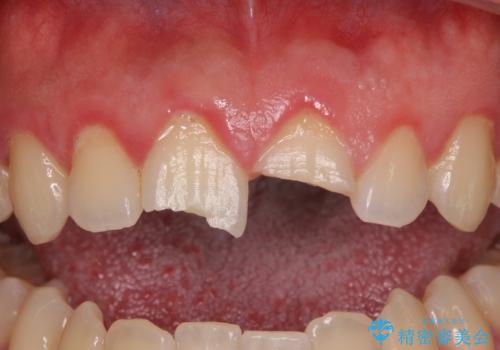

- 酔っ払って転んだらしく、目が覚めたら病室で歯が欠けていたとのことで来院された患者様です。

痛みを感じており、歯の欠けている状況から、神経組織のダメージも想定されました。

無菌的環境下にて歯の状態を調べ、最終的にオールセラミッククラウンにて補綴治療を行うこととしました。